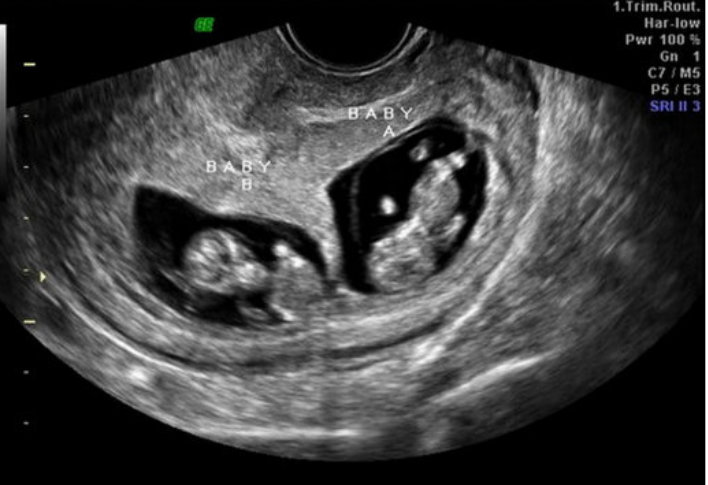

24

Q

A

dichorionic

diamniotic

25

monochorionic monoamniotic

26

dichorionic diamniotic

27

monochorionic diamniotic